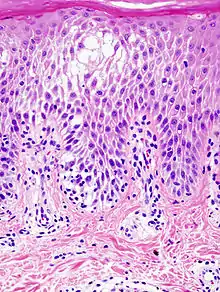

Spongiosis is mainly intercellular[1] edema (abnormal accumulation of fluid) in the epidermis,[2] and is characteristic of eczematous dermatitis, manifested clinically by intraepidermal vesicles (fluid-containing spaces), "juicy" papules, and/or lichenification.[3] It is a severe case of eczema that affects the epidermis, dermis and/or subcutaneous skin tissues.[4][5] The three types of spongiotic dermatitis are acute, subacute and chronic.[5] A dermatologist can diagnose acute spongiotic dermatitis by examining the skin during an office visit but a biopsy is needed for an accurate diagnosis of the type.